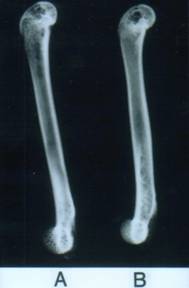

‚t‚l-‚w‚V.‚P‚Æ‚f‚m‚Ì‘å‘Úœ‚̃Œƒ“ƒgƒQƒ“ŽÊ^B‚`‚ª‚t‚l|‚w‚V.‚P‚Å‚a‚ª‚f‚m•‚¢•”•ª‚ª‘½‚¢‚Ù‚Çœ‚ªƒXƒJƒXƒJó‘Ô‚Å‚ ‚邱‚Æ‚ðŽ¦‚·B‚t‚l|‚w‚V.‚P‚Ì•û‚ª‚f‚m‚ɔ䂵‚Ä•‚Á‚Û‚­ŽÊ‚Á‚Ä‚¢‚é‚Ì‚ªŠm”F‚Å‚«‚é

‚t‚l-‚w‚V.‚P‚Æ‚f‚m‚̃Œƒ“ƒgƒQƒ“ŽÊ^